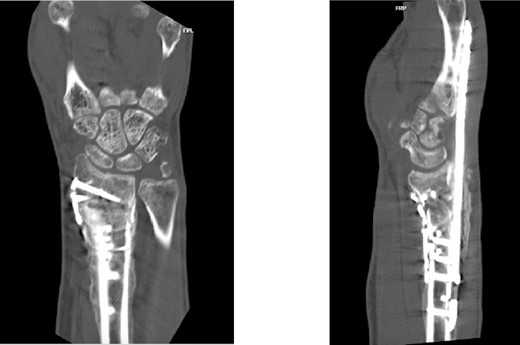

Two weeks following the procedure, the patient returned to the clinic for a follow-up visit. The wrist was swollen and ROM was limited. Hand motor functions and neurovascular exam were fully intact. Radiographs taken in clinic showed intact hardware with healing fracture. At 2 months follow-up, radiographs showed intact hardware with interval bone bridging across fracture sites. Radiographic parameters including articular alignment, radial height, radial inclination, and volar tilt were in acceptable ranges (Fig. 5). The patient reported no concerns or complications. A computed tomography (CT) scan was obtained at 10 weeks after the procedure and confirmed adequate bony healing and alignment without failure (Fig. 6). The dorsal spanning plate was eventually removed 1 month later and 4 months since the initial operation (Fig. 7).

CT assessment at 10 weeks postprocedure with coronal and sagittal cuts.